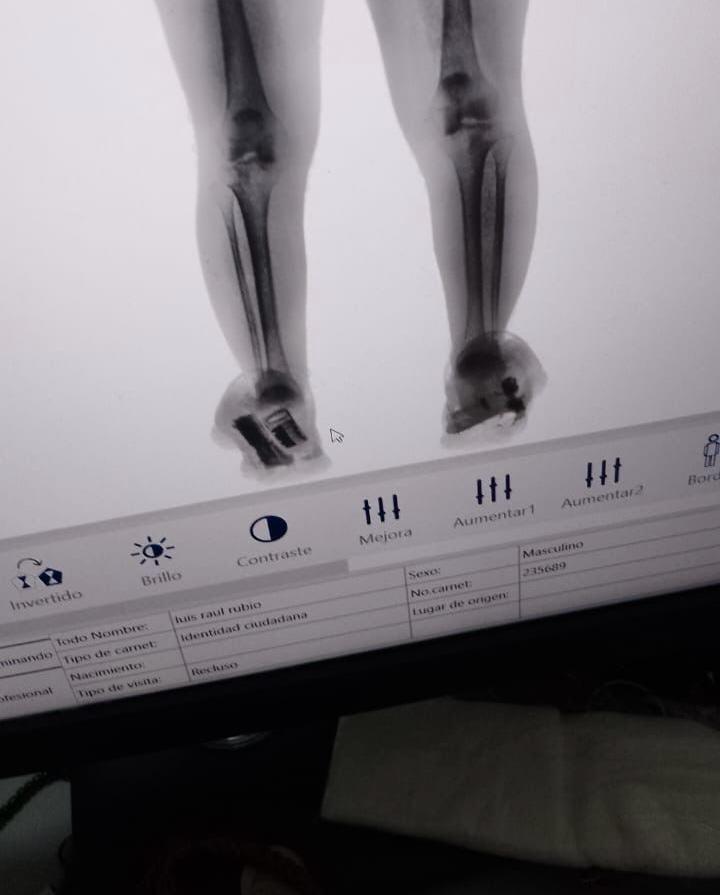

Detienen a mujer que intentó meter arma de fuego al Cereso 1